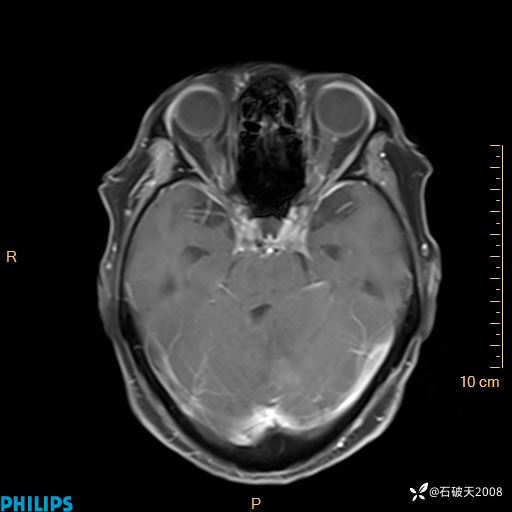

书上说这个肿瘤发生在幕下仅4.09%,你会想到它吗?(病理已公布)

女 86岁 主 诉:乏力1月

现病史:患者1月前活动出现双下肢乏力,无头晕、头痛、恶心、呕吐、肢体活动不利,休息后缓解,间断断发作,症状进行性加重,在家口服药物治疗(具体不详),效差,为进一步诊治,来我院,门诊按“乏力”收住我科,患者自发病以来,神志清,精神稍差,饮食睡眠欠佳,大小便正常,体重未见明显改变。

T2